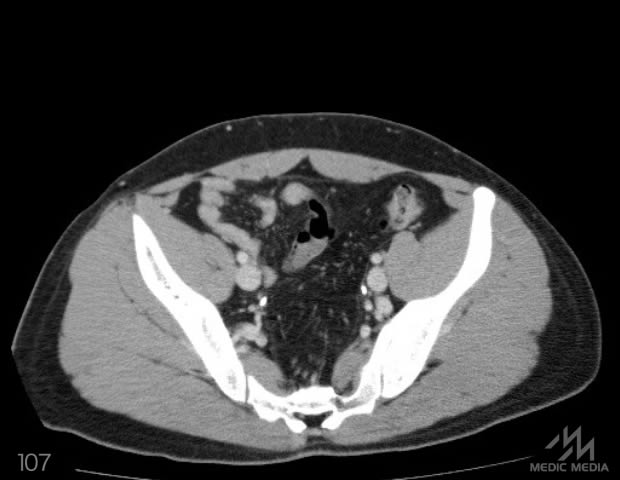

造影CT

スライド(画像下)を動かしながら,CTで臓器の位置を確認してみましょう.

消化器